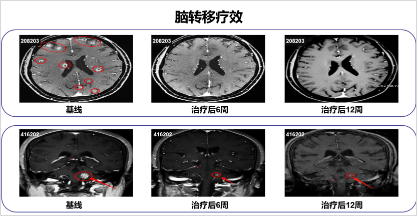

此次大会报告,陆教授介绍了奥美替尼的II期临床试验最新结果。本次研究纳入来自中国大陆和台湾的244例受试者,中位治疗时间为9.5个月(截至2019年5月25日),经独立评审委员会评估,奥美替尼单药治疗客观缓解率(ORR)、疾病控制率(DCR)令人振奋,显示出优异的耐药突变抑制作用;ORR亚组分析表明,奥美替尼在各亚组患者中均有效,其中在脑转移患者中也取得了良好的治疗效果;研究中出现的常见不良反应可耐受,且为临床可控的1或2级水平,3级及以上不良反应发生率和减量、停药率低,研究期间未见患者出现间质性肺病。会后点评环节,世界肺癌大会创始人、连续多届WCLC主席Paul,西班牙著名专家Robust等国际知名专家,高度评价了奥美替尼的研究成果及其与同类国际先进药物在疗效方面的可比拟性。

图3 脑转移病灶治疗效果